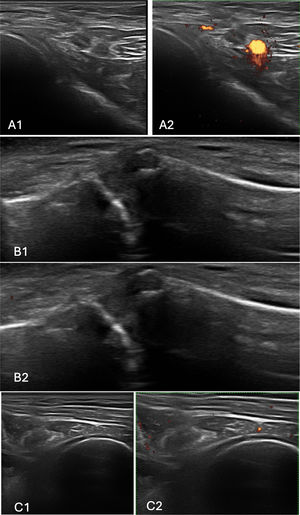

UltrasoundA musculoskeletal ultrasound (MSUS) examination of both shoulders was performed using the scanning technique proposed by the 2017 EULAR standardized procedures for ultrasound imaging in rheumatology.16 MSUS was performed with MyLab50® Xvision equipped with a 5/7.5/10MHz Mindray 7L4a linear probe, guided by an MSUS expert who was blinded to patients’ clinical and laboratory data at the time of the examination. Imaging was required to differentiate and verify RCT from disease activity. The anterior, lateral, and posterior aspects of the joint were scanned. Synovitis was defined according to the published definitions of Outcome Measures in Rheumatology (OMERACT).17 Cases of joint effusion, acromioclavicular synovitis, or glenohumeral synovitis were attributed to RA activity. Representative ultrasound images are shown in Figs. 2 and 3 illustrating findings in a patient with RA without RCT and another with RA+RCT, respectively

Ultrasound findings in a patient with rheumatoid arthritis and rotator cuff tendinopathy. Images of the right shoulder showing degenerative changes in the acromioclavicular and glenohumeral joints, with no evidence of synovitis. (A1) Grayscale longitudinal view of the anterior glenohumeral joint. (A2) Corresponding Doppler image. (B1) Grayscale images of the acromioclavicular joint. (B2) Doppler signal of the same region. (C1) Posterior glenohumeral joint in grayscale. (C2) Corresponding Doppler image.